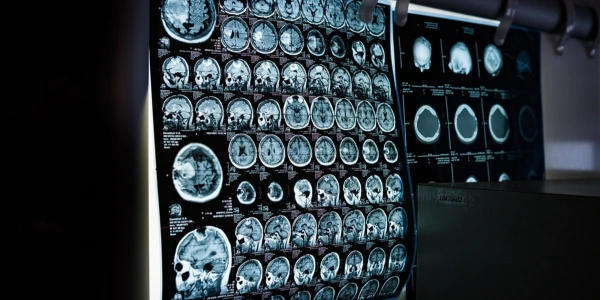

Dématérialisation des services administratifs médicaux : une mutation en cours, toutefois précaire.